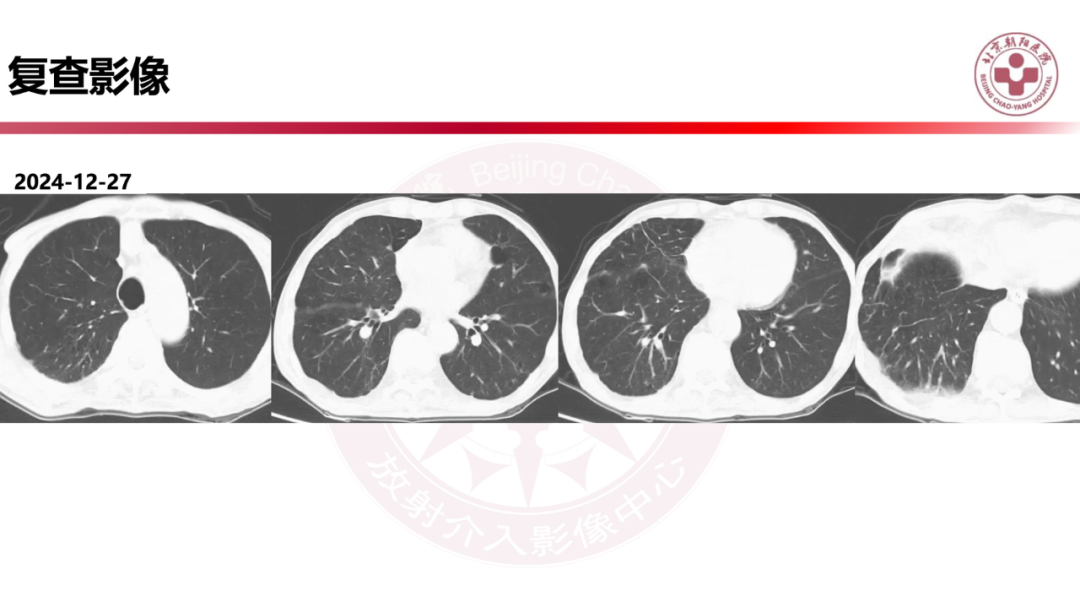

IgG4相关性肺疾病的诊断思路是什么?

来源:北京朝阳医院放射介入影像中心